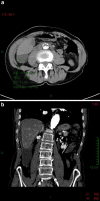

A biloma is an encapsulated collection of bile located in the abdomen. It occurs spontaneously or secondary to traumatic or iatrogenic injury to the biliary system. The patient's medical history, symptoms and diagnostic imaging findings suggest the diagnosis, but a definitive diagnosis is provided by drainage and biochemical analysis of the fluid. We report a case of a patient admitted with acute abdominal pain in the right hypochondrium caused by a spontaneous biloma. This is a rare condition, and the reason for the onset was not identified. We discuss the role of the various diagnostic imaging techniques, particularly that of ultrasound.